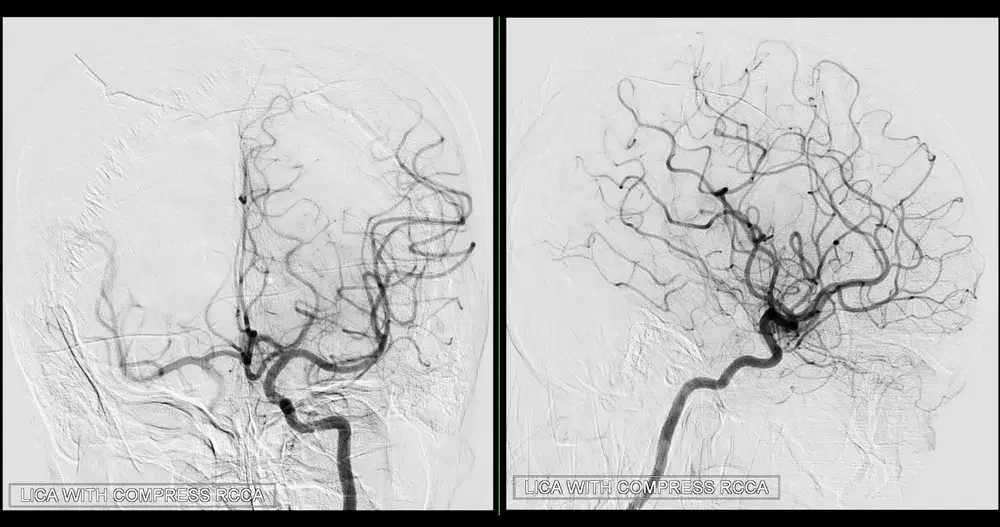

MR Angiography (MRA) is a specialized MRI technique designed to visualize blood vessels, particularly arteries. MRA uses magnetic fields and radio waves to create detailed images of the vascular system.

Time-of-flight MRI is another technique for capturing detailed images of blood vessels. It measures the time it takes for the blood to travel through the vessels, creating high-resolution images of arteries and veins. This technique is especially useful in diagnosing cerebrovascular conditions, such as stroke.

Phase-contrast MRA measures blood flow through vessels and provides images that show both the structure of blood vessels and the direction and speed of blood flow. This technique is valuable for assessing conditions involving abnormal blood flow, such as stenosis or arteriovenous malformations.